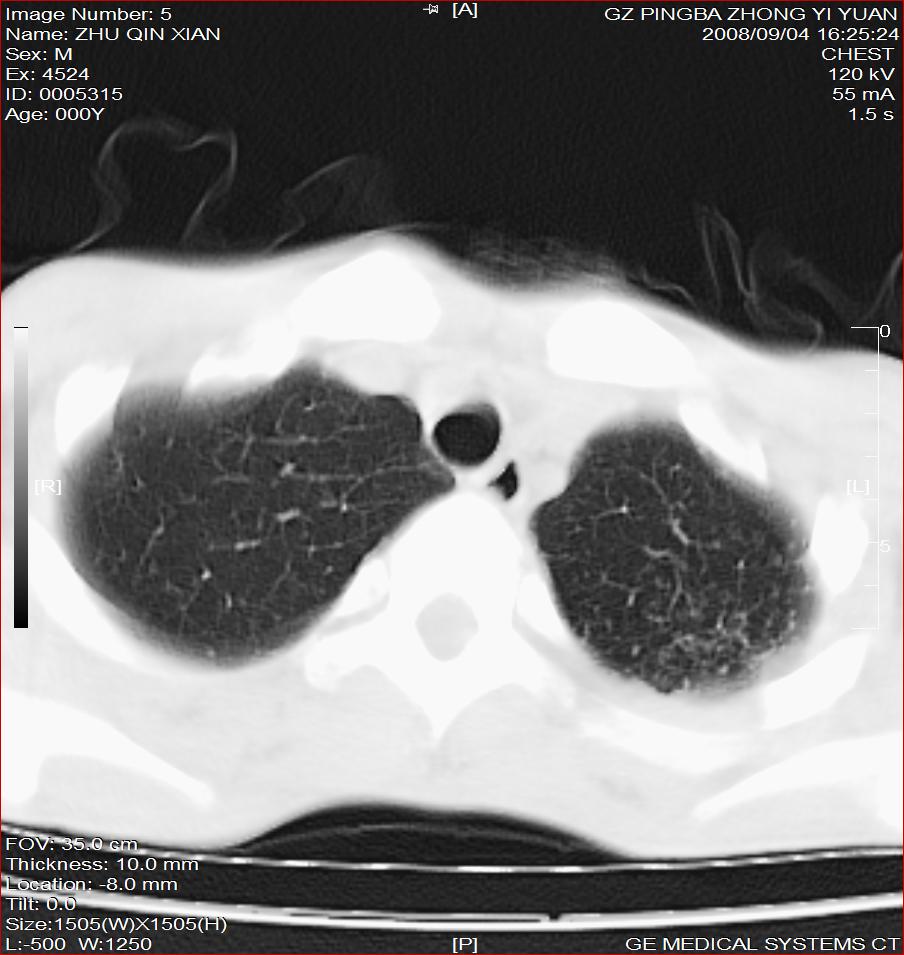

以下是引用随光逐影在2008-9-4 20:05:00的发言:[br]1)考虑两肺结核。2)左侧胸膜炎(胸膜肥厚、粘连,胸腔积液)。3)左侧局限性气胸。

以下是引用子十在2008-9-4 19:34:00的发言:[br]左上肺结核并空洞及双肺播散。节段性肺不张、胸腔积液、胸膜肥厚粘连。[br]